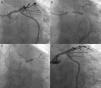

One year later, the patient was readmitted for non-ST elevation myocardial infarction, and the coronary angiogram showed ostial restenosis of the Cx stent (Figure 3A). OCT was performed to better characterize the severity of restenosis and to plan the appropriate revascularization strategy. This technique showed an area of severe restenosis and underexpansion of the Cx ostial stent (Figure 3B-D). In the LM the stent was well apposed and expanded, with only an area of non-significant neointimal growth evident in the proximal stent segment. It was decided to perform percutaneous treatment using a left radial approach and a 7.5F sheathless PB 3.5 Eaucath® (Asahi Intecc) guide catheter. Two guidewires were advanced (LAD and Cx) and the Cx ostium was dilated with a 2 mm×15 mm balloon and a 3.5 mm×15 mm paclitaxel-eluting balloon. The procedure was successfully completed by kissing dilatation with 3.5 mm×15 mm balloons in the LAD and Cx (Figure 3E). The angiographic and OCT result was optimal (Figure 3F and G). At 12-month follow-up, the patient remained asymptomatic.

Second procedure. (A) Angiography showing ostial restenosis of circumflex stent; (B-D) optical coherence tomography (OCT) imaging assessing severity of restenosis, showing underexpansion as the underlying mechanism; (B) proximal circumflex, (C) ostial circumflex, (D) ostial circumflex and bifurcation with left anterior descending artery; (E) kissing balloon inflation; (F and G) final angiography and OCT imaging showing good result.